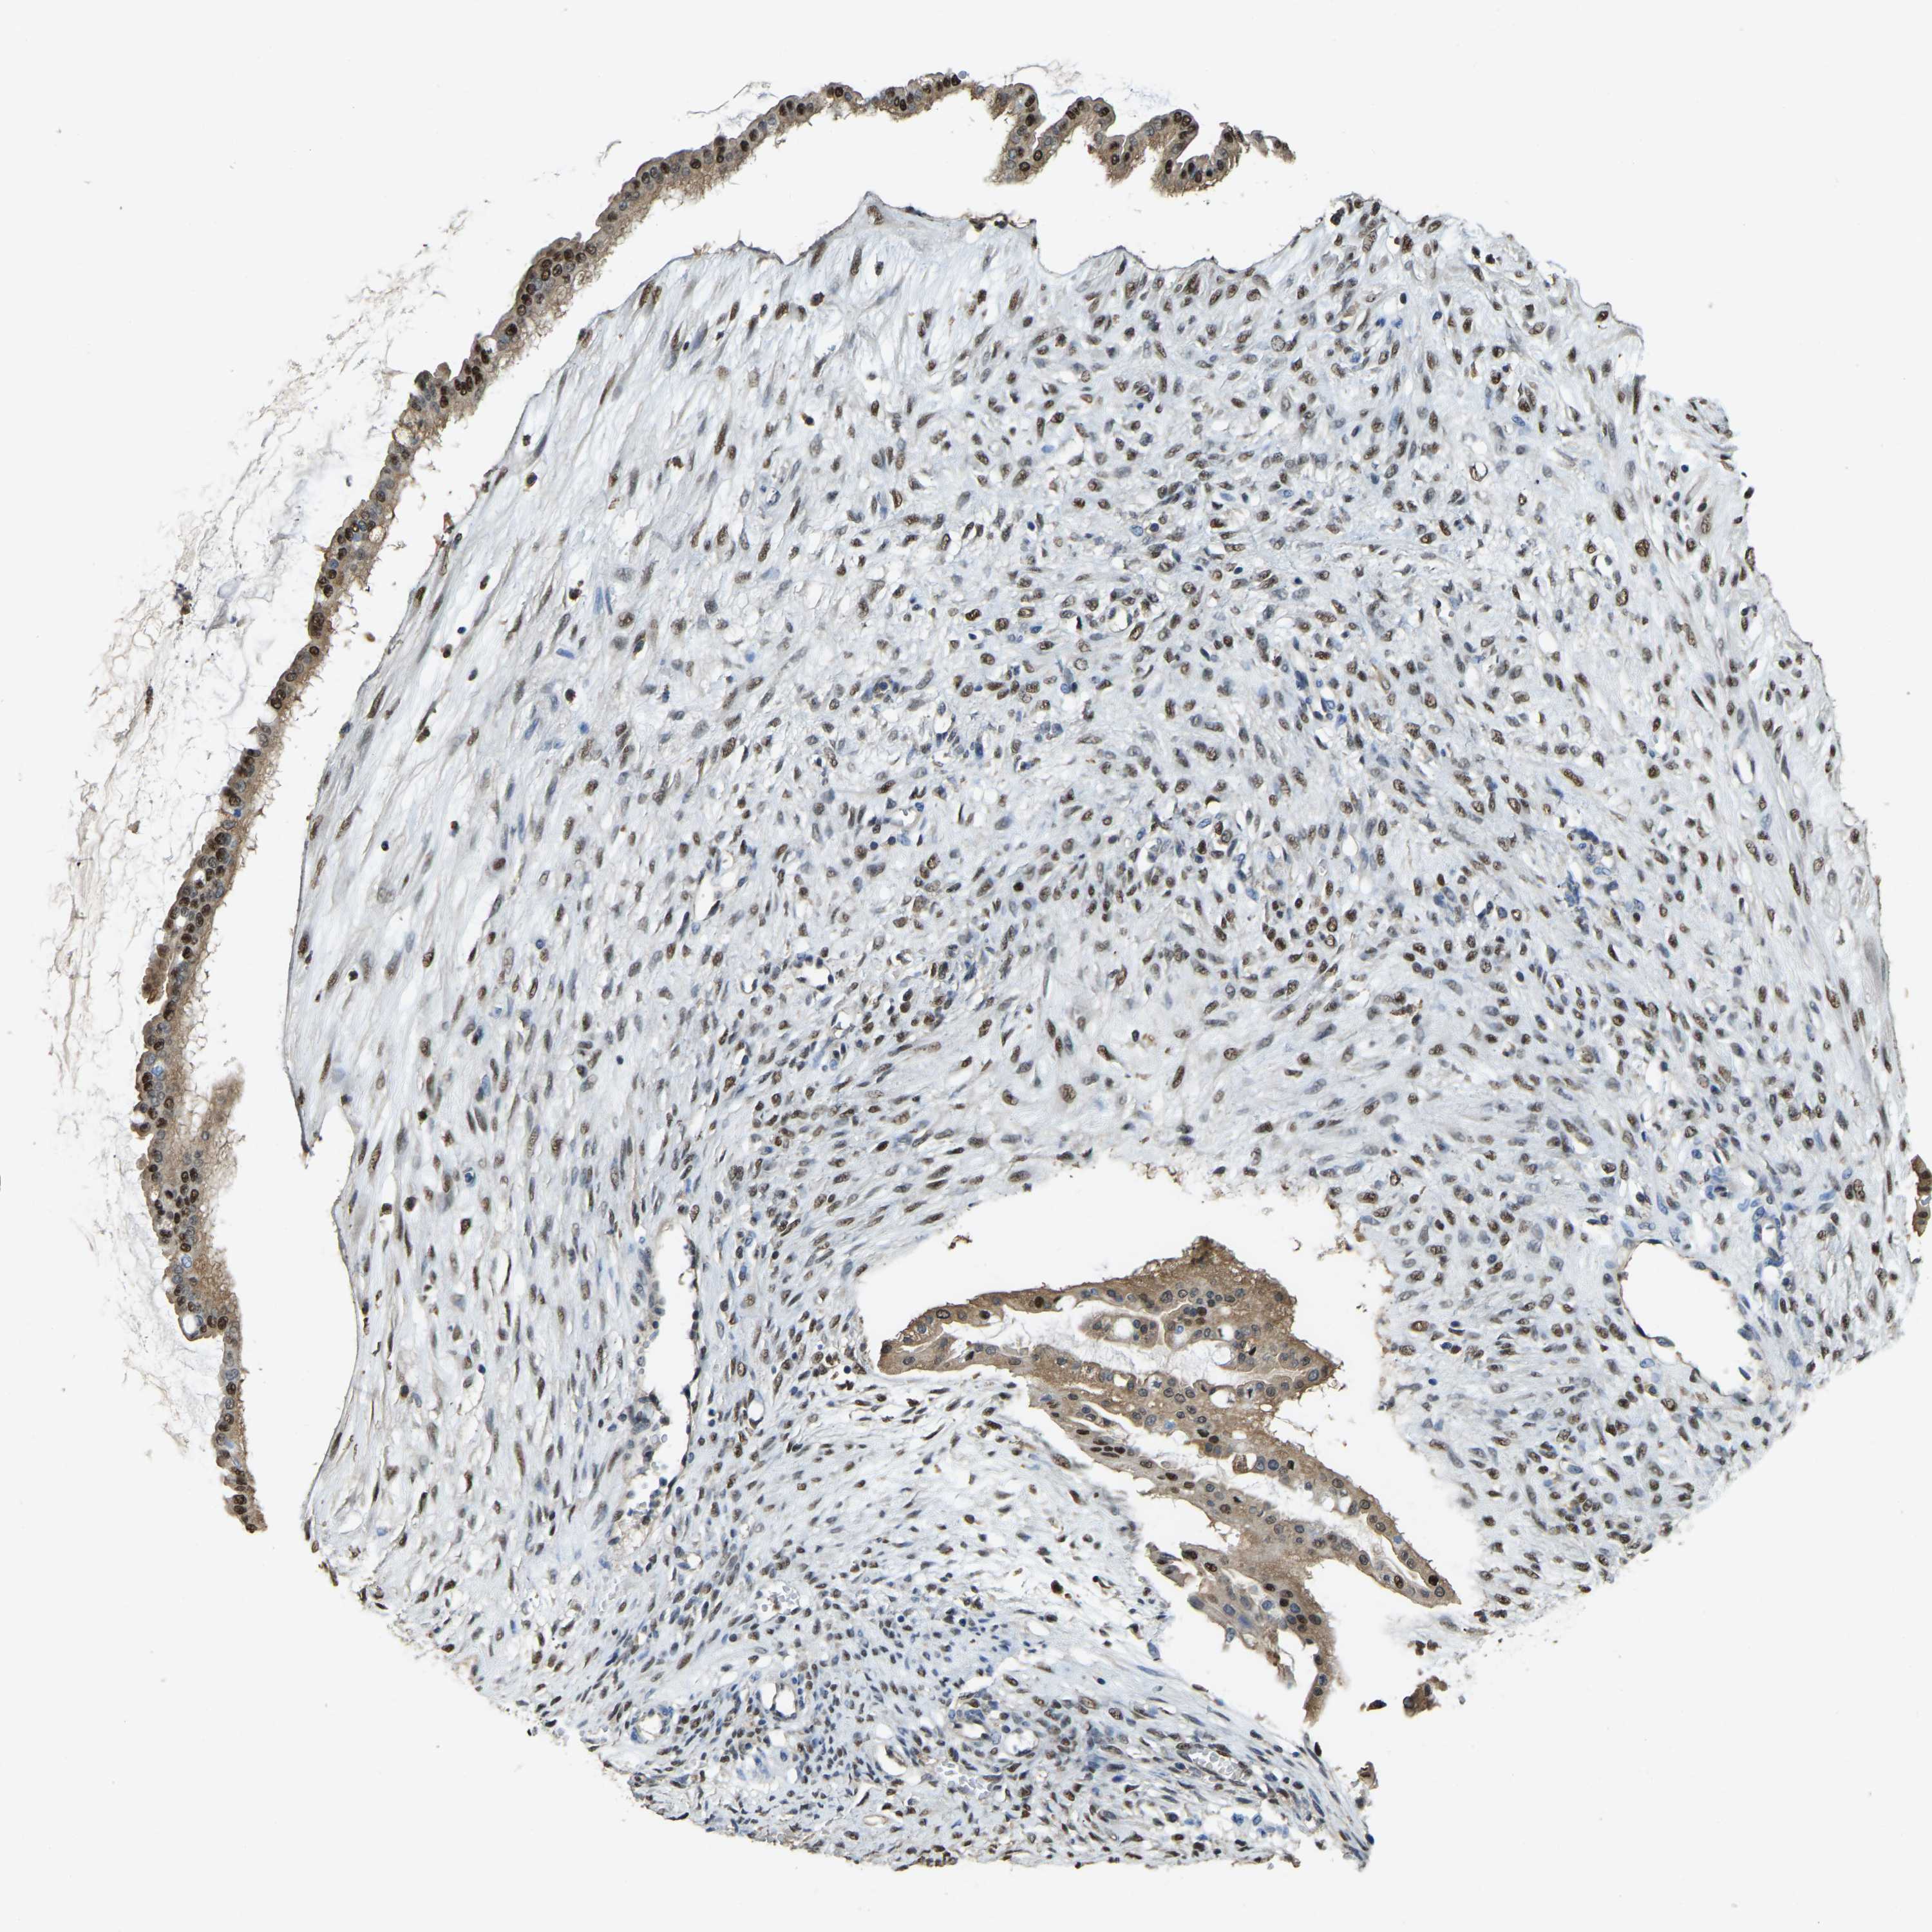

OVARIAN CANCER - Protein expressioni

A mouse-over function shows sample information and annotation data. Click on an image to view it in a full screen mode. Samples can be filtered based on level of antibody staining by selecting one or several of the following categories: high, medium, low and not detected. The assay and annotation is described here.

Note that samples used for immunohistochemistry by the Human Protein Atlas do not correspond to samples in the TCGA dataset.

Antibody stainingi

Antibody staining in the annotated cell types in the current human tissue is reported as not detected, low, medium, or high, based on conventional immunohistochemistry profiling in selected tissues. This score is based on the combination of the staining intensity and fraction of stained cells.

Each image is clickable and will lead to virtual microscopy that enables deeper exploration of all samples and also displays staining intensity scores, fraction scores and subcellular localization as well as patient and tissue information for each sample.

Antibody HPA019223

Staining

High

Medium

Low

Not detected

Intensity

Strong

Moderate

Weak

Negative

Quantity

>75%

75%-25%

<25%

None

Location

Nuclear

Cytoplasmic/membranous

Cytoplasmic/membranous,nuclear

Cystadenocarcinoma, serous, NOS

Carcinoma, endometroid

Cystadenocarcinoma, mucinous, NOS

Carcinoma, NOS